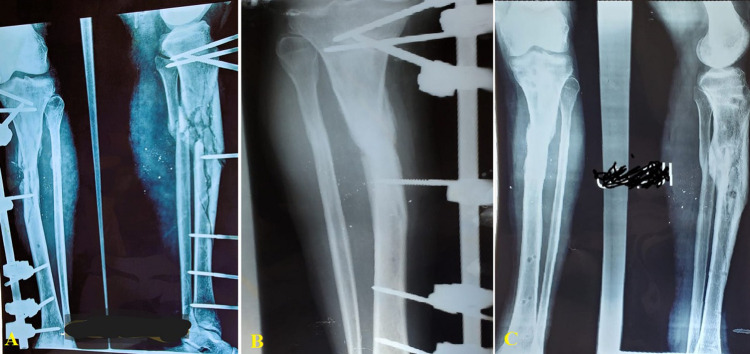

Background: External fixation is one of the most often utilized treatment options for complicated tibial diaphyseal fractures (TDF). The purpose of this study was to assess the efficacy of unilateral external fixators as primary and definitive therapy for complex TDF in a resource-limited setting.

Materials and methods: A retrospective study between June 2016 and March 2021 included 110 subjects with TDF who were treated with an external fixator as definitive fixation in hospitals affiliated with Ibb University. The patient's demographic characteristics, complications, and outcomes were gathered and analyzed. Factors associated with pin site infection were also investigated.

Results: The mean age was 42.1 ± 10.1 years, with 92.7% being male. Rural residents accounted for 22.7%. Smoking and diabetes mellitus were present in 27.3% and 30.0%, respectively. General complications occurred in 12.0%, with pulmonary embolism being the most common at 4.5%. Orthopedic complications included pin-track infections in 27.3% (30) and osteomyelitis in 1.8% (2). Pin site infections required medical treatment in 21 cases and external fixator changes in five. Two cases each needed several debridements for osteomyelitis and soft tissue. Full union occurred in 79.1% (87) over 23.1 ± 3.2 weeks and final alignment in 97.3% (107) over 34.8 ± 4.8 weeks. Malunions occurred in 1.8% (2), and one case had hypertrophic nonunion. Factors like rural residency, smoking, diabetes, open fractures, worst fracture grade (Gustilo and Anderson type C), and general complications occurrence significantly correlated with pin site infection (all p-values < 0.05).

Conclusion: A unilateral external fixator as a primary and definitive treatment is a viable, simple, and effective option for TDF with a high success rate even in a resource-limited setting. In this study, residents in rural areas, smoking, diabetes, open fracture, worst fracture grade, and general complication occurrence were associated with pin site infection occurrence.